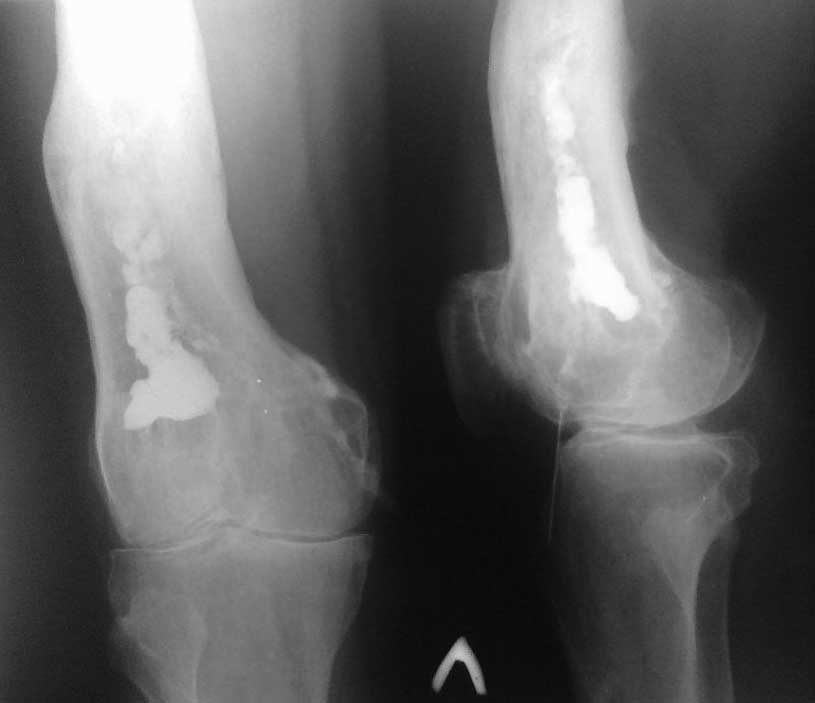

Остеомиелит дистального метафиза бедренной кости |

Уважаемые коллеги помогите определить с тактикой лечении. Больной Т 55 лет. Диагноз: Хронический посттравматический остеомиелит дистального метафиза левой бедренной кости, свищевая форма в стадии обострение, с остеодеструкции костной ткани. Из анамнеза - в 1990 г. получил автодорожную травму. Лечился в ОКБ. Произведена операция - открытая репозиция. интрамед МОС н/3 бедренной кости 2-мя стержнями по Эндеру. Из за нагноение ран металлоконструкция удалена. Через 1 года появилась свищевая рана в н/3 бедра с гнойным отделяемым, с периодическими обострениями. В динамике инфицированная рана (свищ) периодический заживает вторичным натяжением. В 2011 году получал консервативное лечение в ГБ-4 г. Алматы. В данное время вышеуказанные жалобы беспокоят в течение 1 мес. Локально:При осмотре в н/3 левого бедра, область коленного сустава умеренно отечна. В области н/3 левого бедра по передне-латеральной поверхности имеется п/о рубец длиной 12 см, без признаков воспаления. По передне-медиальной поверхности в н/3 бедра имеется свищ 0,7х0,7 см с серозно-гнойным отделяемым. Определяется отечность, болезненность распирающего характера. Движения в коленном суставе (сгибания до160°) ограничено. Чувствительность и движение пальцев лев стопы не нарушены.